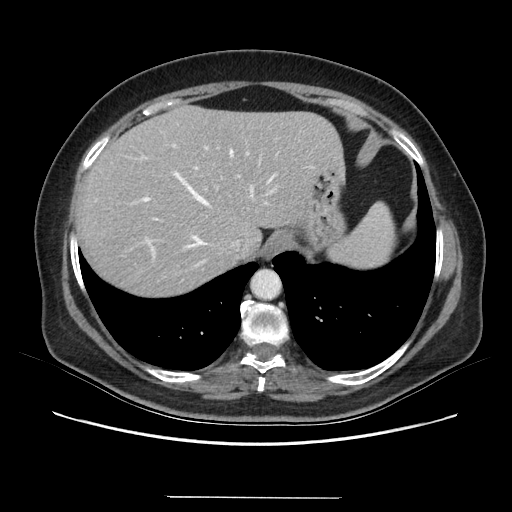

Original VENOUS CT scan

Full window (WL 1023.5, WW 4095 β†’ Low βˆ’1024, High +3071)

Actual HU range: [-160.0, 240.0]